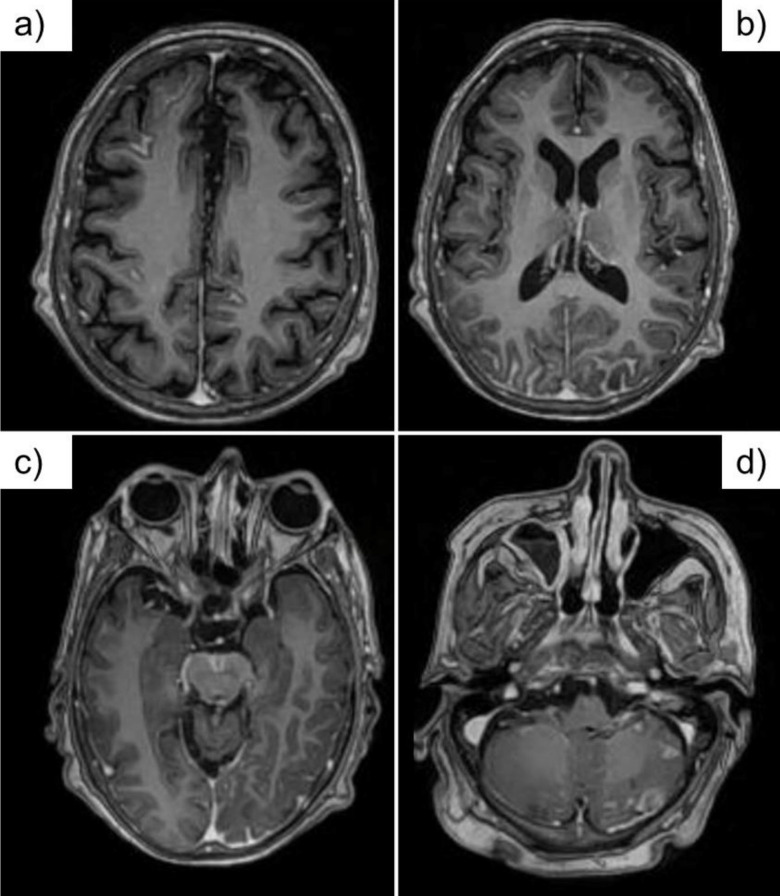

Case report: A 53-year-old woman with chronic hepatic failure, had sudden drowsiness, diplopia, fever, and internuclear ophthalmoplegia. MRI showed generalized leptomeningeal enhancement plus infratentorial nodular enhancement type in the midbrain and left cerebellar hemisphere. An India ink test was positive for Cryptococcus neoformans.